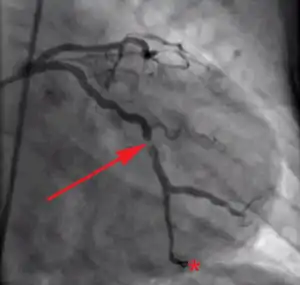

Coronary angiography of a patient with acute myocardial infarction presenting with ST elevation and undergoing primary percutaneous coronary intervention; arrow points at partial occlusion of left circumflex coronary artery; star indicates tip of the guide wire that has been inserted in the artery through the occlusion.

Coronary angiography of the same patient, after dilation of the artery with balloon and placement of stent. The occlusion has been successfully treated.[51]